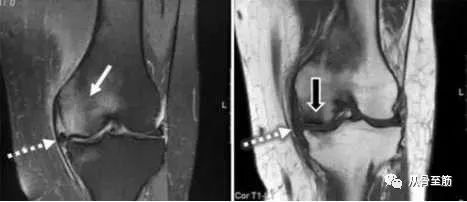

? ? 骨髓水肿这个名词,是随着磁共振成像(MRI)技术的应用而出现的,也就是说,只有在MRI检查中才能发现这种现象。病变区在MRI的T2WI压脂像上白,在T1WI上黑,与软组织水肿的影像学改变相似,故称为骨髓水肿。其他影像检查不能够发现或诊断骨髓水肿(包括X线片、CT、超声等)。“骨髓水肿”并不是独立的疾病,只是某些疾病中的表现之一或某一阶段。就像关节腔积液不是一个独立疾病一样。外伤造成的骨髓水肿通常称为骨挫伤或隐匿性骨折,这是由于骨小梁的微骨折,引起局部的出血水肿和局部微细结构的改变。

? ? 骨髓水肿可见于1、骨感染性疾病:如骨髓炎、结核;2、骨关节外伤:特别是X光片无明显骨折的挫伤;3、肿瘤,转移性病变更明显;4、骨的缺血性疾病:如股骨头坏死、距骨坏死;5、骨关节免疫性疾病:最常见的是类风湿性关节炎、强直性脊柱炎等;5、退行性骨关节病;血液系统的疾病:白血病,骨髓瘤等;7、其他:中毒性骨病,如镉中毒等造成骨溶解而伴骨髓水肿;痛风性关节病等。

? ? MRI是目前诊断、评价骨髓水肿的最佳手段。疼痛的程度与骨髓水肿的严重程度相一致,随着MRI骨髓水肿严重程度的减退,患者的疼痛的程度也相应减轻。发现骨髓水肿,首先应查明病因,积极治疗原发病。